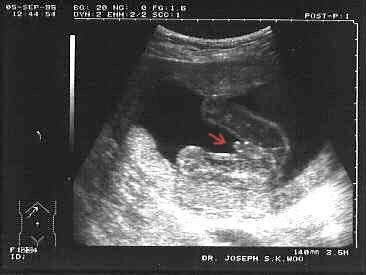

Posílám dva snímky, červenou šipkou je označeno pohlaví (děvče, chlapec).

Mužské pohlaví